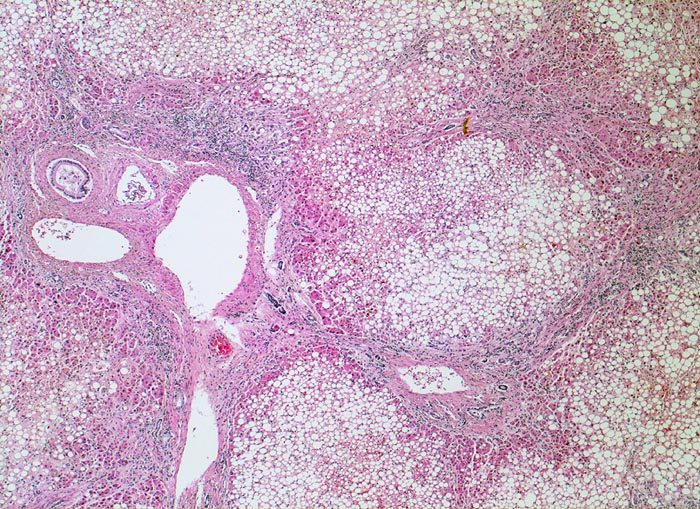

PathoPic – image database / PathoPic ID 4765 - alkoholische Leberzirrhose, Steatose

alkoholische Leberzirrhose, Steatose

Bindgewebebige Septen verbinden die Portalfelder und führen zur Ausbildung kleiner Knoten. Ca. 80% der Hepatozyten sind grobtropfig verfettet.

Die alkoholische Leberzirrhose ist bei fortgesetztem Alkoholabusus typischerweise feinknotig (Knotengrösse makroskopisch <3mm)